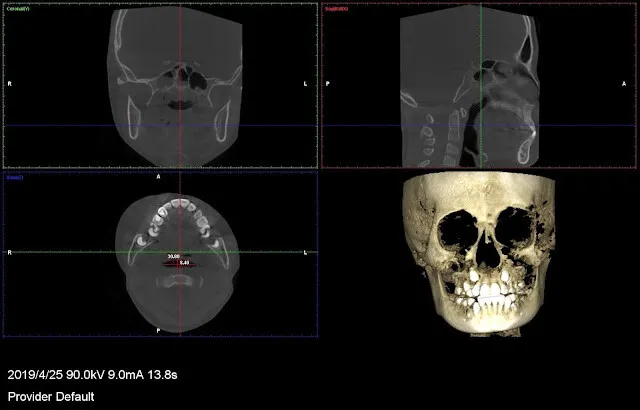

以上是CT斷層掃瞄,我會測量呼吸道(氣管咽喉部分)的寬度,有數值的,一張是平均,一張是最窄處。